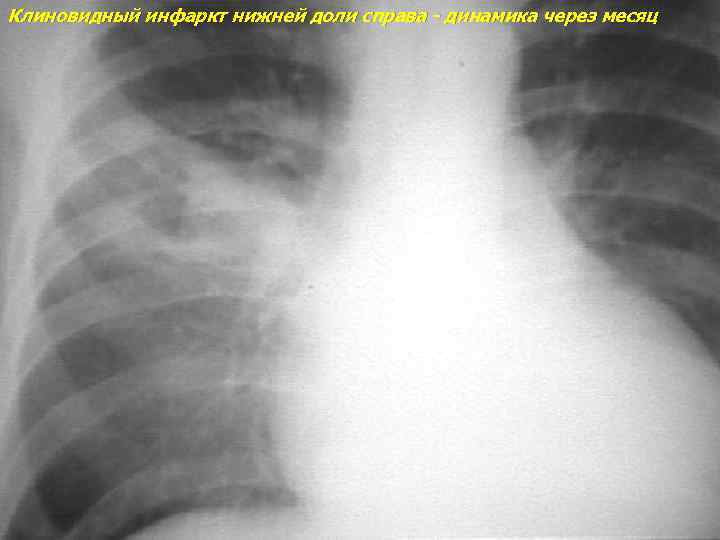

Клиновидный инфаркт нижней доли справа - динамика через месяц